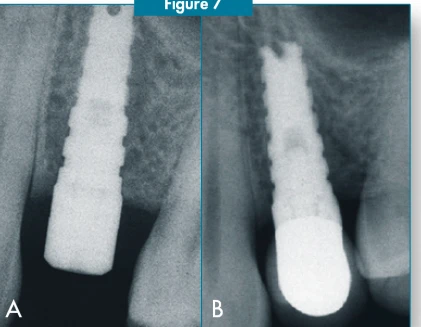

Implant Apical Feature: Grooves and Apical Notch.

Platform to Abutment Connection: Parabolic Platform. 3.5mmx5.5mmx5.1mm.